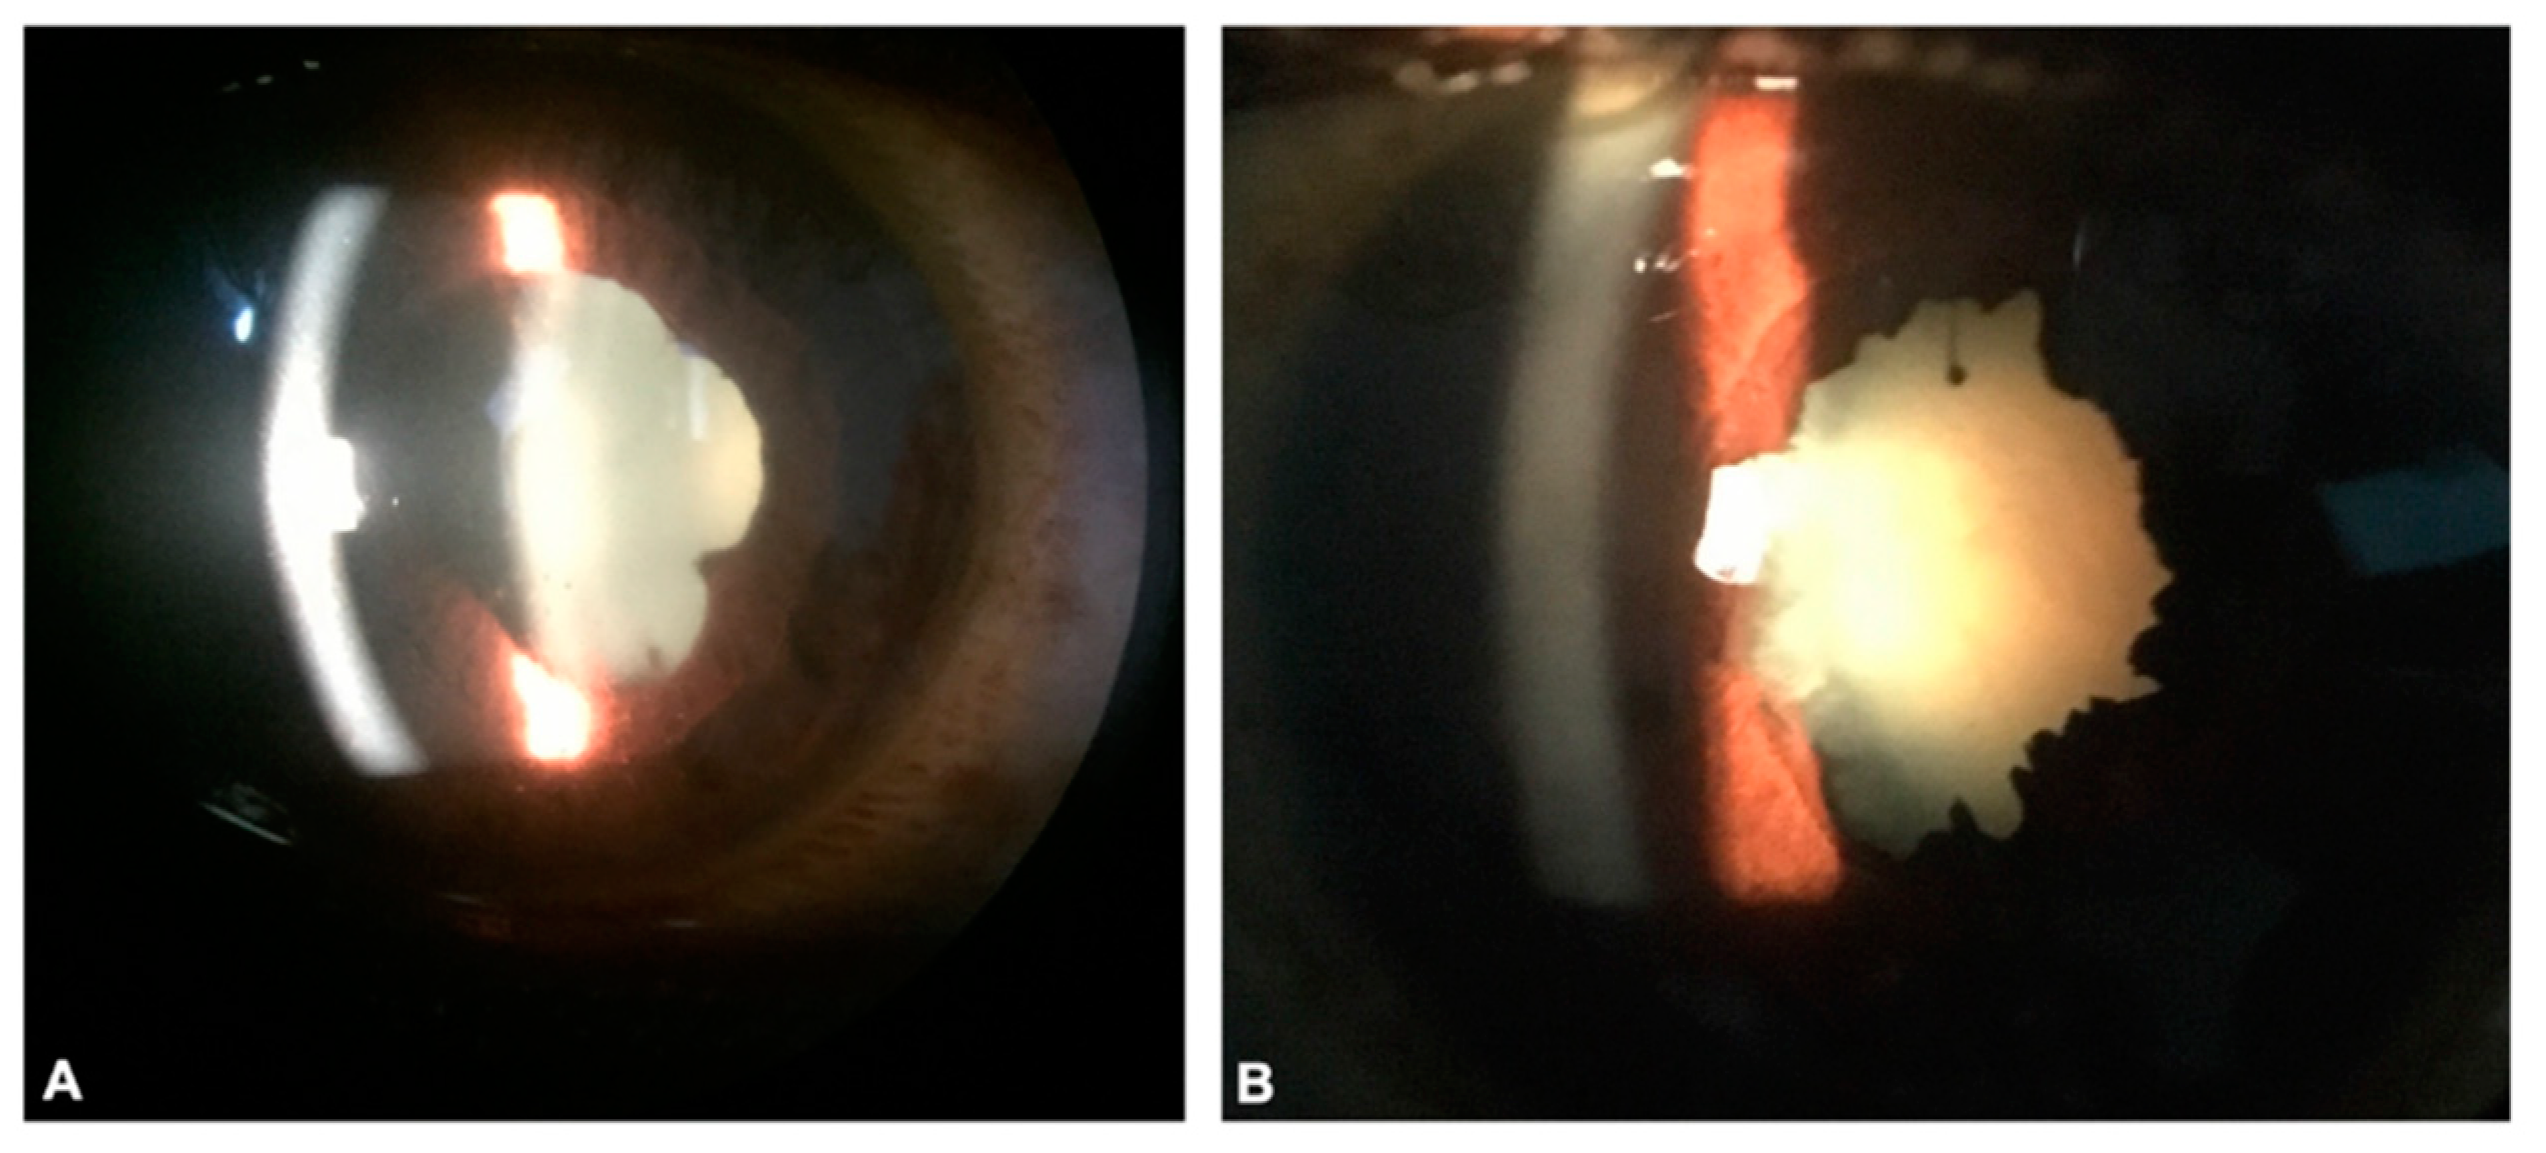

| Lassa fever | Mammarenavirus (Arenavirus) | West Africa- Sierra Leone, Guinea, Liberia, and Nigeria. [9] | Fever, sore throat, vomiting, malaise. Neurological complications including hearing loss in severe cases. [29,30] | Acute Lassa fever: Conjunctivitis Convalescence: cataract, chorioretinal scarring, retinal fibrosis, and vitreous opacity noticed. Anterior uveitis, iritis. [31,32] | Visual acuity worsened in LHF survivors with ophthalmic manifestations. [32] |